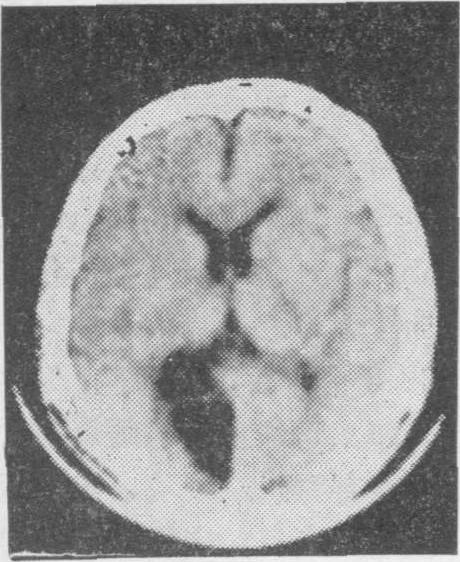

老年人脑血管病的诊断主要依靠详细询问病史,仔细观察临床症状和体征,并结合各种筛选检查。一般先用非创伤性检查,如脑电图、脑超声波、Doppler超声波、放射性核素脑扫描或计算机X线体层脑扫描检查等。特别是后者对老年人急性脑血管病的鉴别诊断更有帮助,可以鉴别是脑出血性病变(图3),脑缺血性病变(图4),抑或脑部肿瘤,以后根据需要再进行创伤性检查,如脑血管造影等。

图3 脑出血性病变的计算